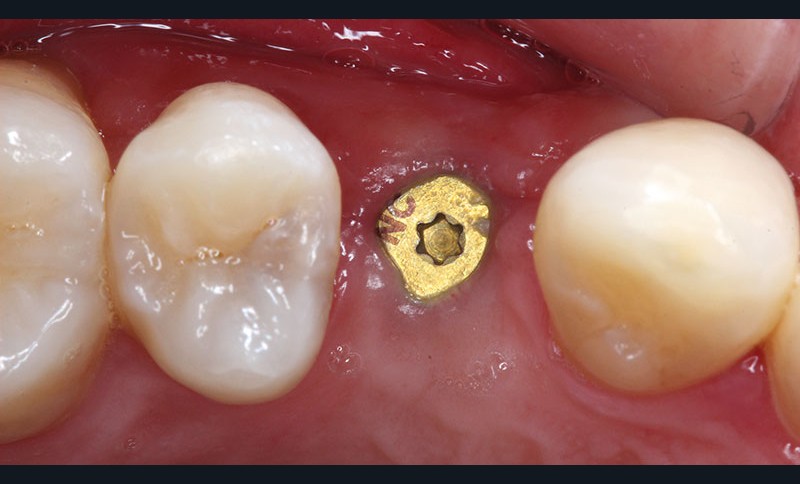

Examen clinique

Un jeune patient consulte pour combler un édentement unitaire en 14. Un implant dentaire (Bone Level NC®, Straumann) est mis en place en respectant un projet prothétique ayant pour finalité une prothèse implantaire transvissée. Après trois mois, l’ostéointégration est validée cliniquement et radiologiquement, la réhabilitation prothétique peut alors débuter (fig. 1).